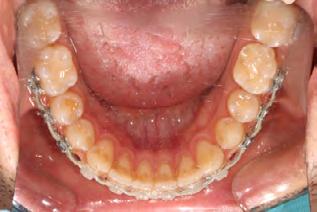

Palatal mini-implants were placed by a periodontist, followed by placement of the rapid palatal expander (RPE) and bonding of the mandibular arch with self-ligating Damon clear braces. Patient had SARPE surgery performed by the oral surgeon three weeks later (Figure 2), and the expander was turned once a day for three weeks (Figure 3). The maxillary arch was then bonded. Both archwires were incremen-

Figure 1. Initial records.

tally upgraded to an 18 x 25 NiTi wire, and the patient was placed on vertical elastics on the right side. With enough space for the tongue, the lateral open bite began to close.